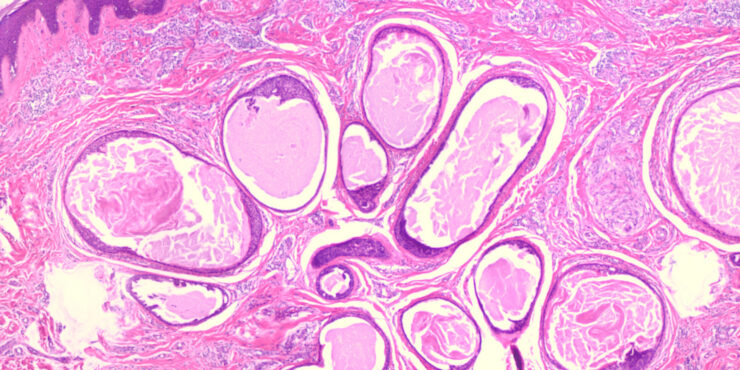

Papillary eccrine adenoma = الغدوم الناتح الحطاطي

Papillary eccrine adenoma = الغدوم الناتح الحطاطي OLYMPUS DIGITAL CAMERA OLYMPUS DIGITAL CAMERA